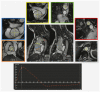

Recently, medical radiology has undergone significant improvements in patient management due to advancements in image acquisition by the last generation of machines, data processing, and the integration of artificial intelligence. In this way, cardiovascular imaging is one of the fastest-growing radiological subspecialties. In this study, a compressive review was focused on addressing how and why CT and MR have gained a I class indication in most cardiovascular diseases, and the potential impact of tissue and functional characterization by CT photon counting, quantitative MR mapping, and 4-D flow. Regarding rectal imaging, advances in cancer imaging using diffusion-weighted MRI sequences for identifying residual disease after neoadjuvant chemoradiotherapy and [18F] FDG PET/MRI were provided for high-resolution anatomical and functional data in oncological patients. The results present a large overview of the approach to the imaging of diffuse and focal liver diseases by US elastography, contrast-enhanced US, quantitative MRI, and CT for patient risk stratification. Italy is currently riding the wave of these improvements. The development of large networks will be crucial to create high-quality databases for patient-centered precision medicine using artificial intelligence. Dedicated radiologists with specific training and a close relationship with the referring clinicians will be essential human factors.